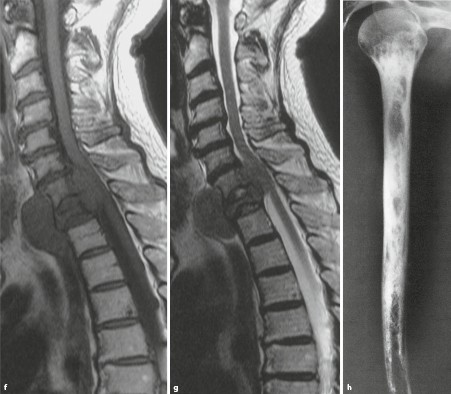

Kortikale arrosion. 2 a a 40 year woman came with recurrent painful swelling of left face since 4 months. Ct scan showed a soft tissue density lesion involving left maxillary antrum with erosion of lateral wall of the maxillary sinus and the floor of left orbit. Cortical erosion refers to destruction of cortex by a lytic or sclerotic process.

Erosion of periarticular cortical bone the typical feature observed on plain radiographs in patients with rheumatoid arthritis results from excessive local bone resorption and inadequate bone formation. Epiphyseal metaphyseal or diaphyseal. Thinning of he cortex by an intraosseous process does not indicate cortical erosion but suggests endosteal scalloping.

Central within the bone eccentric or cortical. Metastases and myeloma will usually occur in patients over the age of 40. In chondrosarcoma unicameral bone cyst non ossifying fibroma may cause cortical erosion with minimal periosteal response in an aneurysmal bone cyst or giant cell tumor the cortex may be completely destroyed but a thin layer of periosteal neo corticalization may surround the lesion.